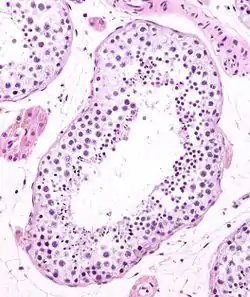

Seminiferous tubule (right) with sperm (black, tiny, ovoid). H&E stain.

Seminiferous tubule (transverse section).